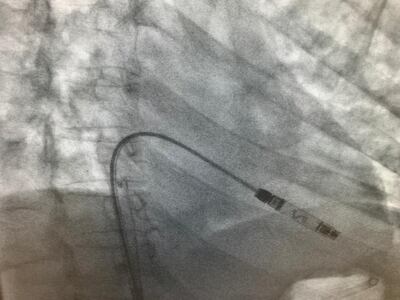

Leadless pacemakers are miniaturised devices implanted using a catheter in the thigh vein and then implanted directly into the heart.

The device has a unique mapping capability designed to allow physicians to measure electrical signals within the heart and determine the correct placement of the device before final implantation, Abbot said.